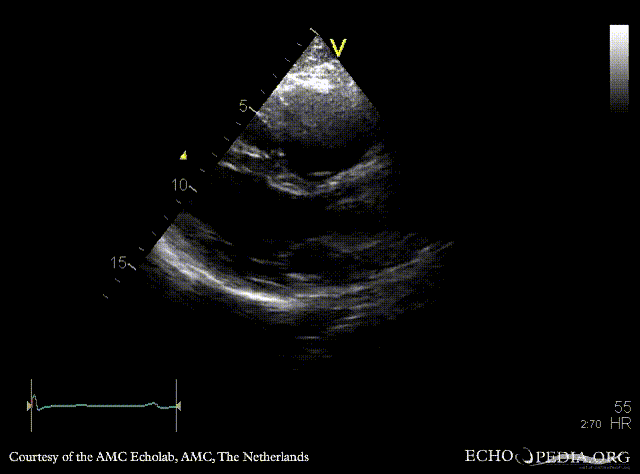

ARVD

Courtesy of: AMC Echolab, AMC, The Netherlands

PLAX: right ventricle dilatation in patient with ARVD PSAX: dilated right ventricle